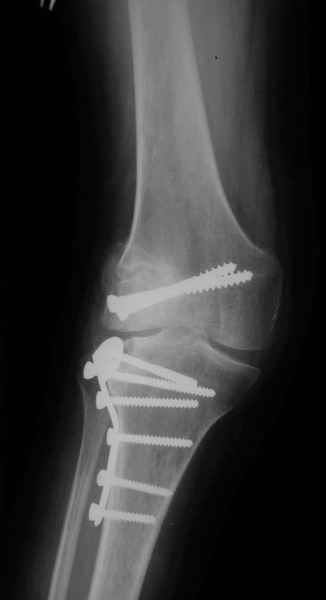

Как вариант решения прогрессирующей вальгусной деформации коленного сустава я бы предложил косую остеотомию дистального отдела бедра с фиксацией пластиной и компрессирующим винтом.

Взгляните на снимки , может быть это вам поможет.

Около 5 лет применяю этот тип дистальной остеотомии бедра для коррекции механической оси Н/К ( более 20 случаев) - достаточно эффективная операция.

Было одно осложнение у молодого пациента - ятрогенное повреждение бедренной артрерии, которое решилось васкулярной пластикой без каких -либо последствий для функции конечности.